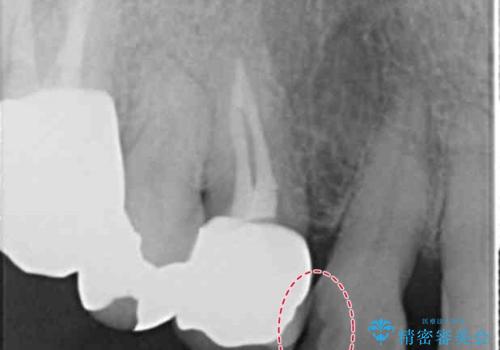

- 前歯が欠けたとのことで来院。

確認すると上の前歯の裏側に大きな虫歯がありました。

- 右上2 仮歯+ジルコニアクラウン(スタンダード) 11000円+110000円費用は治療当時の料金となります